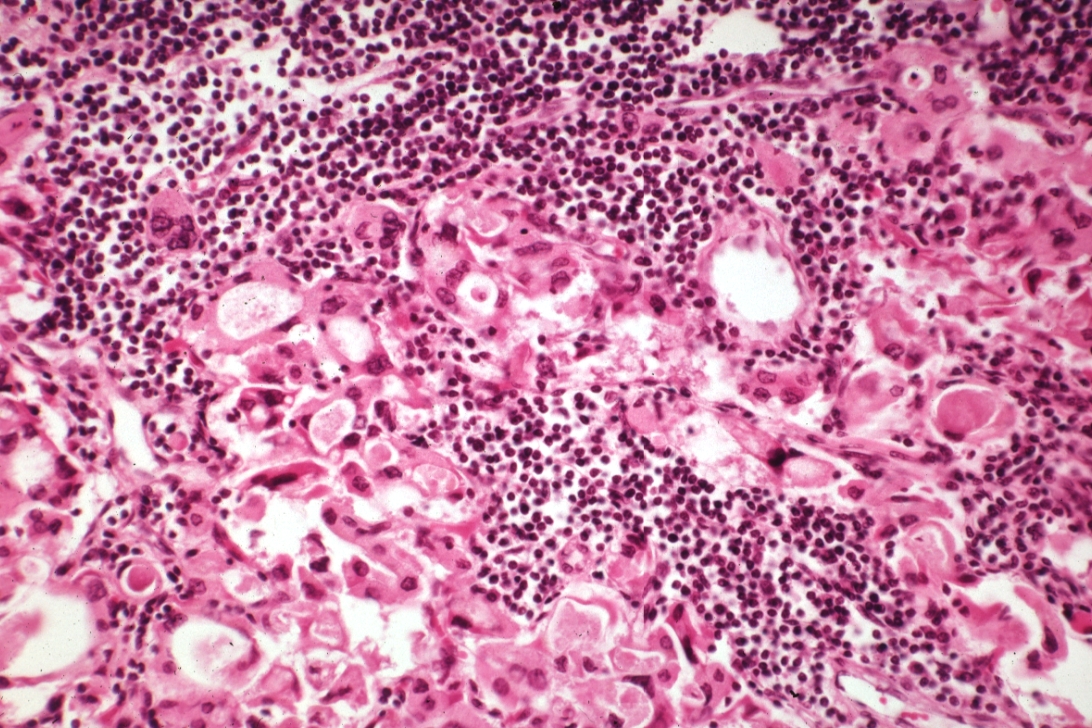

HISTOLOGY: ENDOCRINE: Thyroid: Lymphocytic Thyroiditis: High mag H&E excellent example of cell injury